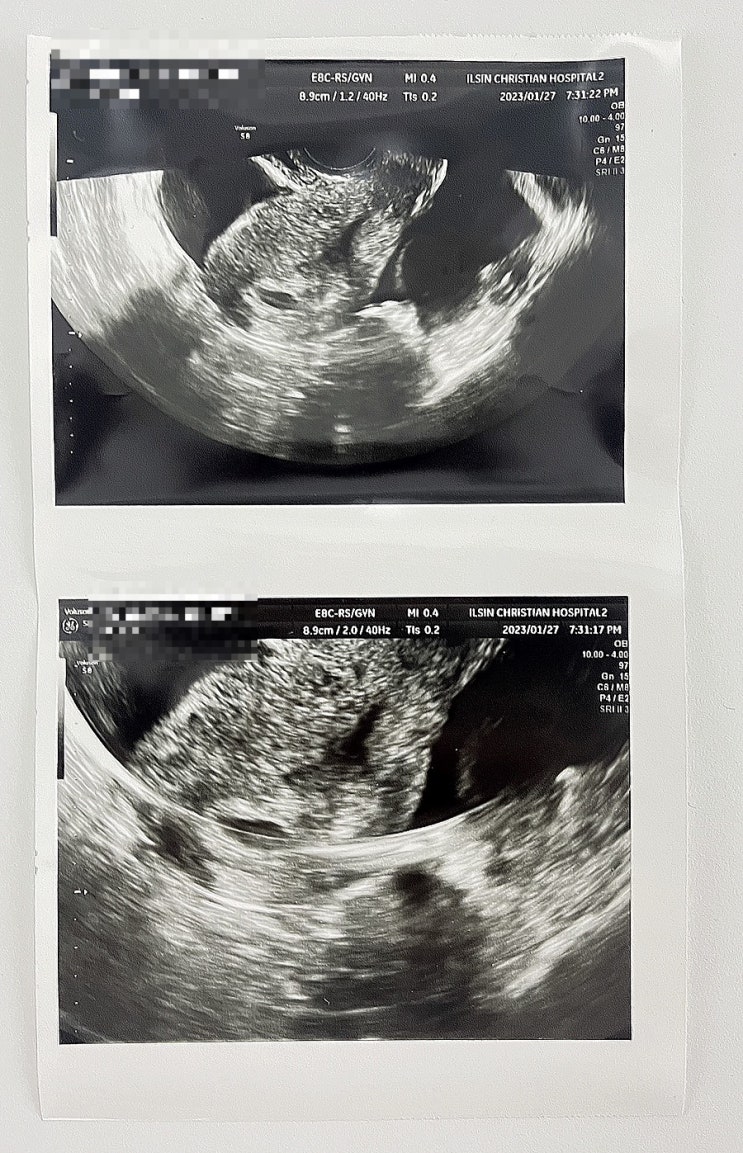

[임신 5주차/6주차] 일주일만에 드라마틱한 초음파 변화(난황, 심장소리)& 보건소 물건수령 후기

전 테스트기로 임신확인 후 3일 후에 병원 갔었어요 그때가 5주차였었는데 첫 초음파때 난황도 안보이고 아...